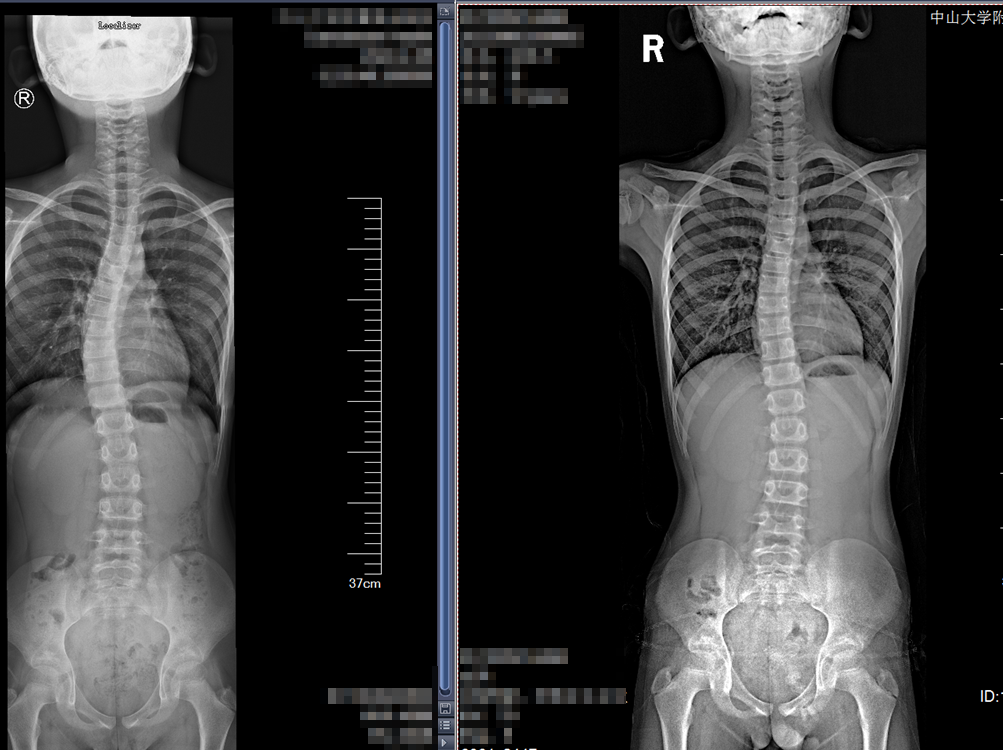

12岁的小谭长期坐姿不良,直到家长发现其身体偏斜严重时才到中大五院就诊,检查提示她的脊柱侧弯达46度。

矫正前后对比图

脊柱外科吕海主任评估病情后,认为患儿脊柱发育尚不成熟,柔韧度尚可,建议暂不手术,进行矫正支具治疗,并根据病情变化,及时更换定制支具。经过2年的积极干预,目前,她的脊柱侧弯已经矫正到17度,正进一步恢复中。